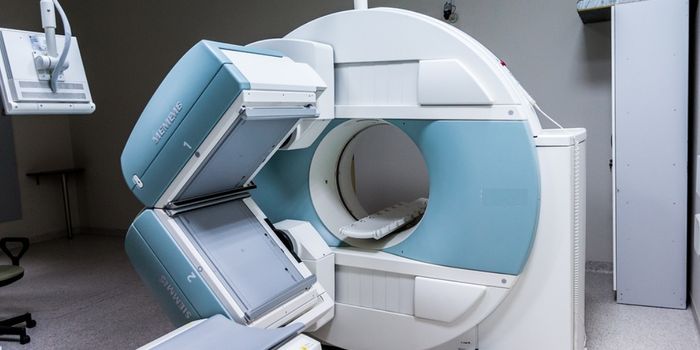

APR 03, 2018Clinical & Molecular DXScientists are improving the way PET scans work to detect diseases as early as possible with a new imaging agent. Focusi ...

SEP 14, 2017CancerLarry King, the famed talk show host, recently revealed his diagnosis of Stage 1 lung cancer. King then underwent surger ...

APR 07, 2016CancerLung cancer is the second most common form of cancer in both men and women. With such a high incidence rate and an equal ...

JUN 19, 2025CancerLow-dose computed tomography (LDCT), a technique that uses X-rays to create detailed images of the lungs, has shown effi ...

MAY 25, 2025CancerComputed tomography (CT) examinations (known more commonly as a “CT scan” or “CAT scan”) incorpo ...